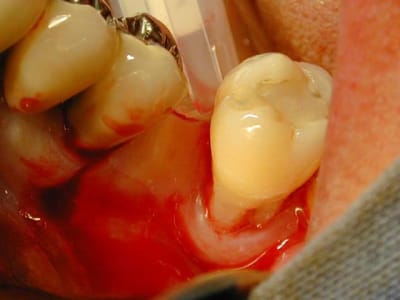

Cher Monsieur alhoun dit le Sakharov du Forum, si vous voulez bien aider un petit jeune qui débute, je prépare mon polycop de bizarrodontologie clinique et je voulais votre avis sur ce summers non conventionnel dans un cadre un peu étriqué.

Hé Galilée c'est parce que la 7, mème d'aprés les critères des penseurs de Capbreton a un avenir limité et va être extraite et implantée. Or implanter là c'est pas forcément de la tarte.

Dans l'espace interdentaire le sinus est invaginé. Donc plutot qu'extraire et greffer pourquoi ne pas summeriser entre les deux en comptant sur la vascularisation venant de la dent puis on extraiera ensuite. Torquemada aussi peut donner son avis, hein. Voyez mes efforts pour rétablir la paix sur ce forum, et resserer des liens distordus par les invectives de mes confrères vétilleux.